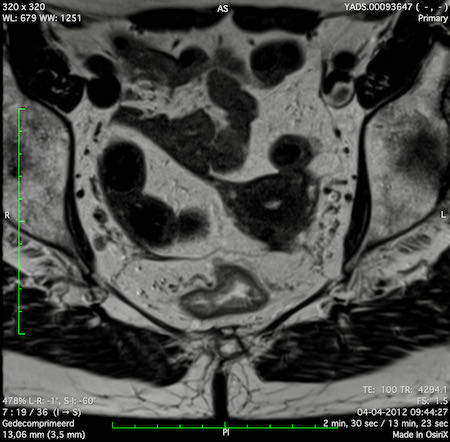

Hình ảnh

Các hình ảnh được cung cấp cho thấy ung thư biểu mô tế bào nhẫn với tình trạng dày lan tỏa thành trực tràng, hình ảnh bia bắn điển hình, và sự xâm lấn mỡ mạc treo trực tràng.